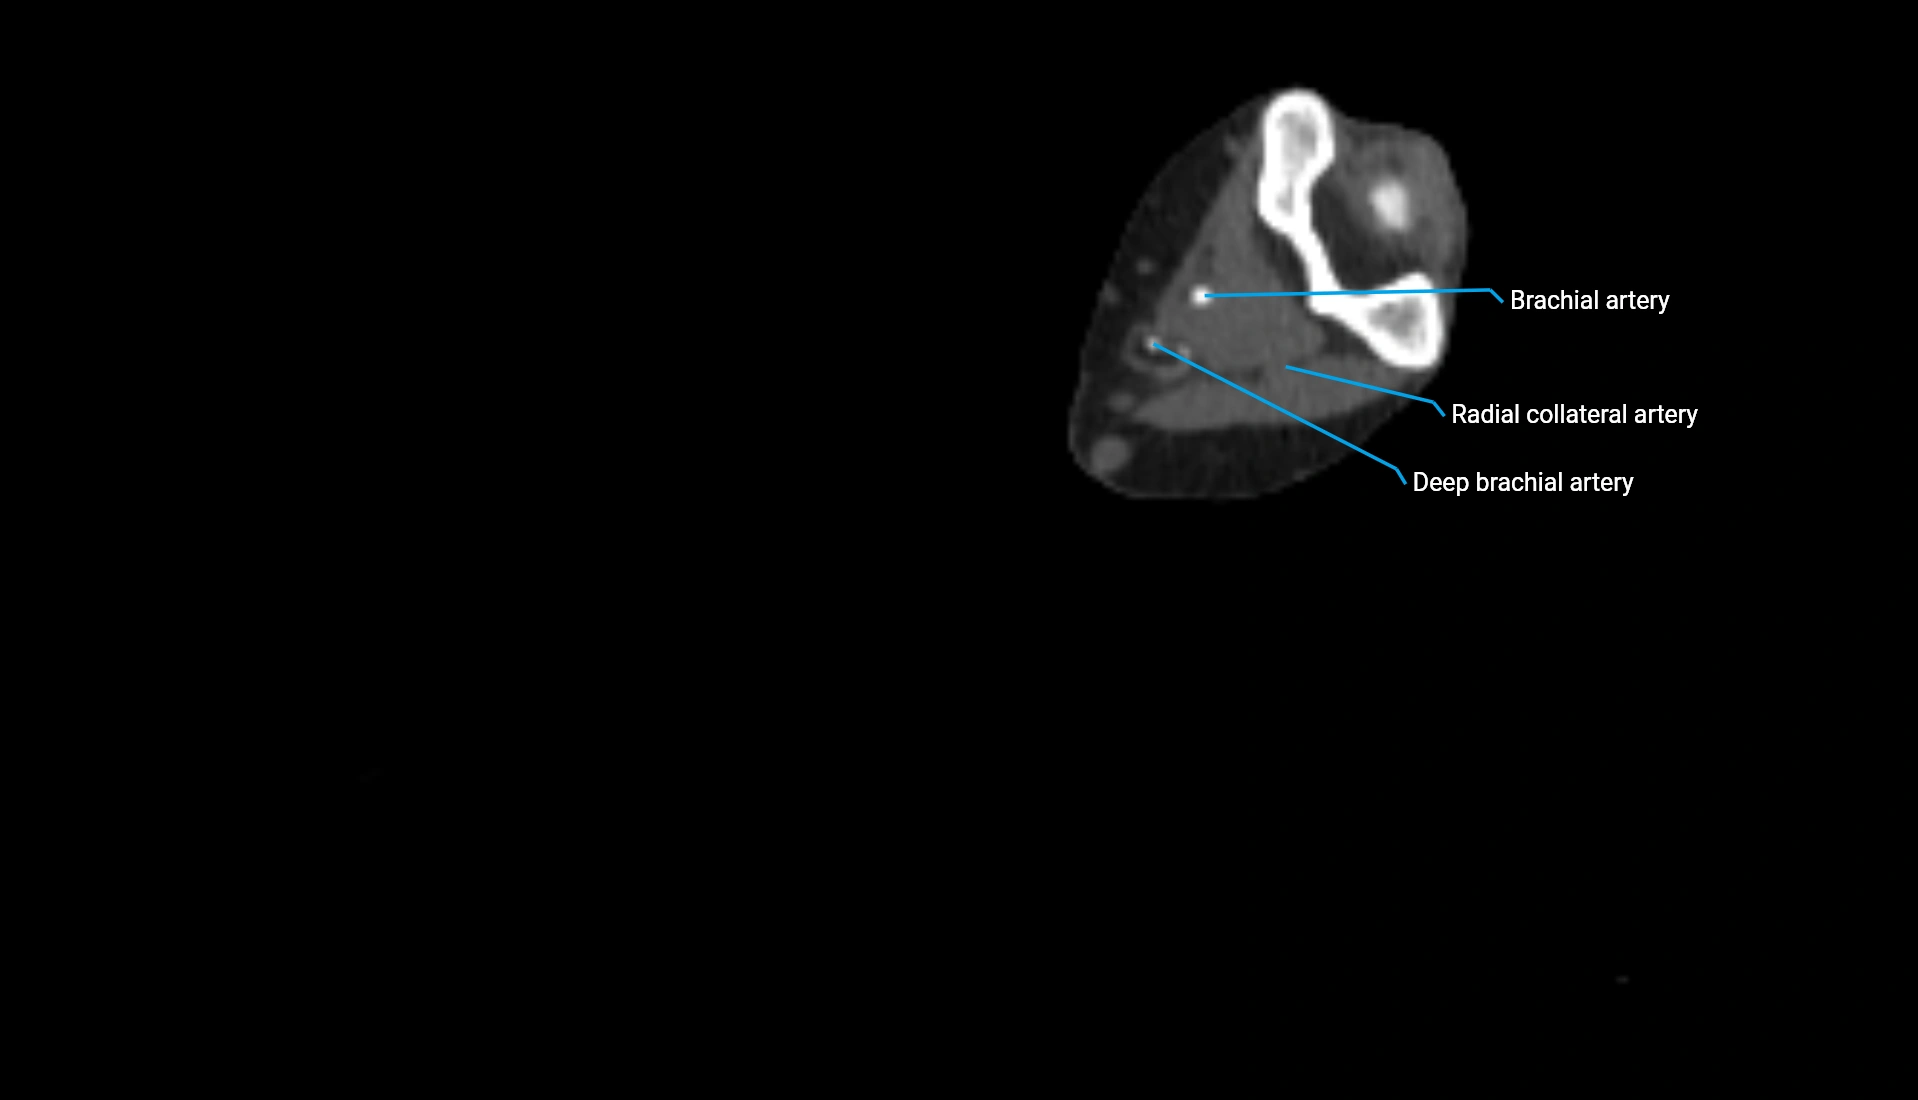

CT Appearance

Non-Contrast CT:

• Cortex: High-density, sharply defined

• Subchondral bone: Dense cancellous matrix

• Articular surface: Smooth concave contour articulating with the capitellum

• Excellent for evaluating bone integrity, alignment, and subtle fractures